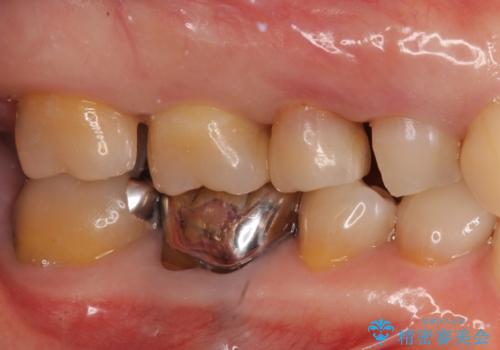

銀歯を白く 虫歯治療

- 虫歯治療を希望して来院。

保険適用の銀色のつめもののやり替えを行いました。

- 30.8万円(右上4567 emaxプレスインレー 7万円x4本)費用は治療当時の料金となります